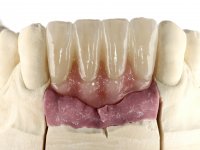

Após estudo imagiológico foi planificada a colocação de dois implantes de 3.3 mm de diâmetro e 10 mm de comprimento. No dia da cirurgia foram extraídos os dentes 42 e 32 e removido o implante. Os implantes foram colocados na zona dos alvéolos tendo o cuidado de lingualizar um pouco o seu posicionamento. Foi feita uma impressão pela técnica de moldeira aberta com o retalho aberto para a confeção da ponte provisória imediata. Enquanto a impressão foi para o laboratório, foram colocados parafusos de cicatrização altos e feita a sutura da ferida cirúrgica. A paciente esperou 2 horas na sala de espera enquanto no laboratório era confecionada a ponte provisória. A ponte provisória imediata aparafusada foi colocada e o seu assentamento controlado imagiologicmente. Passados 3 meses foi realizada a impressão definitiva com uma técnica de moldeira aberta. Nessa consulta aproveitamos para polir a ponte provisória com taças de borracha para que os tecidos moles pudessem maturar em melhores condições. Foi feita a recolha de informação para caracterizar da melhor forma a estrutura monolítica em Zr. Foram utilizadas guias de cor para a cerâmica de tonalidade coronária e gengival. No laboratório foi confecionada uma ponte em Zr. aparafusada que foi cuidadosamente caracterizada. Após aprovação pela paciente foi colocada definitivamente em boca. O aperto foi feito com uma chave dinâmica com 35 N de torque. Os orifícios foram tapados com teflon e obturados com resina composta.